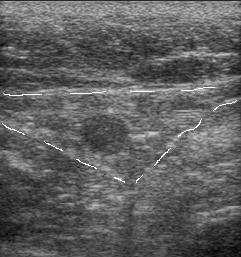

Вены и артерии на узи мониторе в так называемом В-режиме видны как черные, анэхогенные "реки", что является прямым признаком жидкого однородного содержимого.

Повышения вязкости крови ведет к появлению эхогенности внутрисосудистого содержимого. Стенка у вен намного тоньше артериальной, и в норме всегда меньше 1 мм, не имеет деления на слои. Артериальная хорошо видна, дифференциация на слои отчетливая. При обследовании вен оценивают ее стенку, диаметр просвета, однородность просвета, внутрипросветные структуры, реакцию на функциональные пробы, как в черно-белом режиме, так и с цветовым кодированием кровотока. При проведении проб, на вдохе вены расширяются, работоспособные клапаны не пропускают кровь в противоположном направлении (от сердца к периферии), что отражается при цветовом кодировании кровотока как отсутствие цвета, в патологии же, цвет меняется на противоположный.

Особенно актуально это при подозрении на тромбоз глубоких вен. Существуют два прямых признака

венозного тромбоза по узи: внутрипросветные включения и некомпрессируемость (несжимаемость)

датчиком.